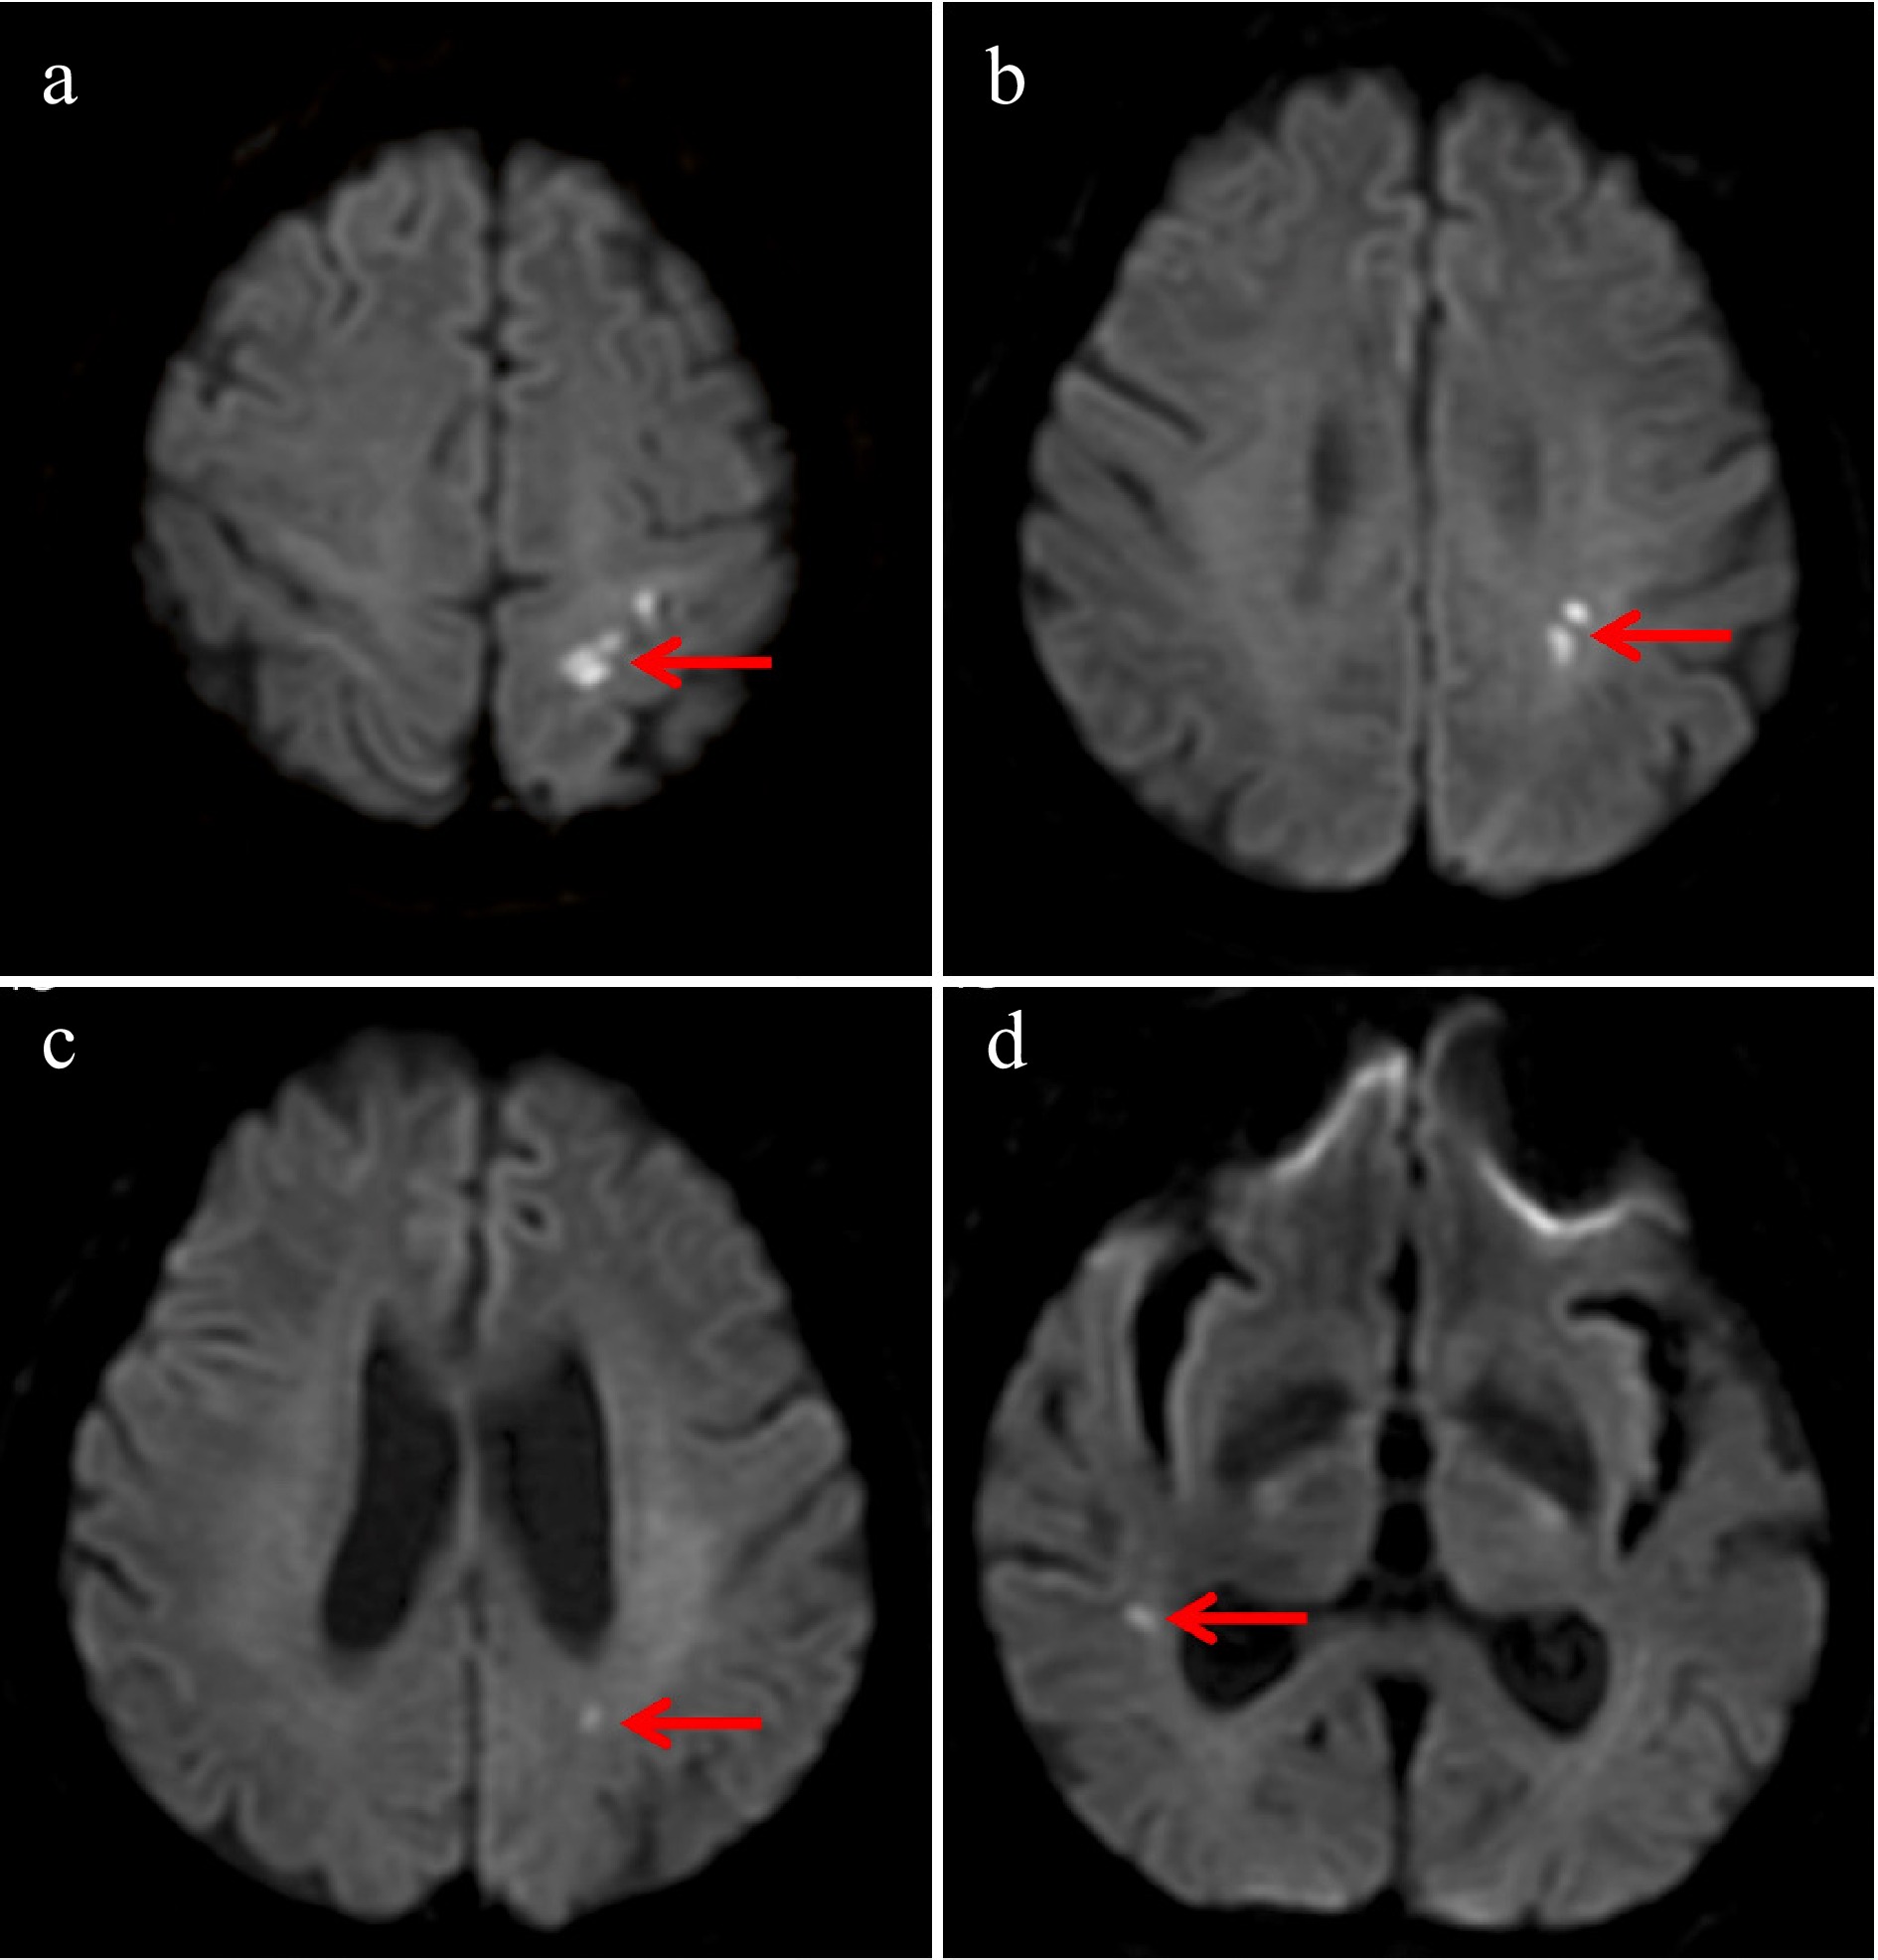

A 74-year-old man was admitted to a local hospital following the acute onset of right-sided limb weakness. Brain magnetic resonance imaging (MRI)–diffusion-weighted imaging (DWI) revealed an AMCI involving bilateral anterior and posterior circulations (Fig. 1). Initial laboratory investigations demonstrated an elevated serum carcinoembryonic antigen (CEA) level of 12.68 ng/mL (normal range: 0−5.2 ng/mL) and a significantly reduced hemoglobin level of 88 g/L (normal range: 130−175 g/L), indicative of anemia and potential malignancy.

Figure 1.

Brain magnetic resonance imaging–diffusion-weighted imaging (MRI-DWI) demonstrated multiple cerebral infarctions involving both the anterior and posterior circulations. Acute infarction in (a) the left anterior cerebral artery (ACA) region, (b) the left middle cerebral artery (MCA) region, (c) the left posterior cerebral artery (PCA) region, and (d) the right MCA region.

When discussing cancer-related stroke, Trousseau's syndrome is a critical concept. First described by French physician Armand Trousseau in 1865, this syndrome represents a spectrum of clinical manifestations, resulting from a cancer-associated hypercoagulable state. It is recognized as a type of paraneoplastic syndrome and represents the second leading cause of death in cancer patients, surpassed only by the malignancy itself[18]. AMCI is a well-documented manifestation of Trousseau's syndrome and can even be its initial presentation[4,19]. Although no universally accepted diagnostic criteria exist, several key features are characteristic. Neuroimaging often reveals multiple small infarcts across multiple vascular territories, with the "three territory sign" (TTS) (involving the bilateral anterior and posterior circulation) holding significant diagnostic value[20]. Furthermore, markedly elevated D-dimer levels are a common laboratory finding[14,21,22]. As a product of fibrin degradation, D-dimer is a sensitive, though nonspecific, biomarker of coagulation activation and thrombosis; its elevation indicates a systemic hypercoagulable state and has been identified as an independent risk factor for cancer-related stroke. Crucially, since acute multiple cerebral infarcts in MRI-DWI are not pathognomonic for Trousseau's syndrome and are also observed in cardiogenic embolism (most frequently atrial fibrillation)[23], a comprehensive work-up including electrocardiography (ECG) and echocardiography is mandatory to exclude cardioembolic sources before attributing the stroke to Trousseau's syndrome.

Applying these diagnostic considerations to our patient, a definitive diagnosis of Trousseau's syndrome remains challenging, despite suggestive features. Although the patient had confirmed active malignancy and the MRI-DWI demonstrated the TTS, several critical factors preclude a conclusive diagnosis. First, the absence of universally accepted diagnostic criteria for Trousseau's syndrome introduces inherent ambiguity. Second, the patient's D-dimer level was only mildly elevated (1.3 mg/L; normal range: 0–0.5 mg/L), contrasting with the markedly elevated levels typically reported in classic cases. Third, although routine ECG and transthoracic echocardiography (TTE) revealed no abnormalities, the inherent limitations of TTE in detecting left atrial appendage thrombi and nonbacterial thrombotic endocarditis (NBTE) compared with transesophageal echocardiography (TEE), coupled with the absence of prolonged Holter monitoring to exclude paroxysmal atrial fibrillation, mean that potential cardioembolic sources cannot be fully eliminated. Finally, the contribution of traditional stroke risk factors (advanced age, hypertension, smoking history) cannot be entirely disentangled from a potential paraneoplastic mechanism. Therefore, although Trousseau's syndrome represents a plausible diagnostic consideration, this case is most accurately classified as cryptogenic stroke representing the initial manifestation of occult systemic malignancies.

This diagnostic dilemma underscores that routine cancer screening is not warranted for all cryptogenic stroke patients because of the cost considerations. However, the presence of specific clinical indicators—including bilateral infarctions or TTS on MRI-DWI, particularly when combined with elevated D-dimer levels and relevant tumor markers such as carcinoembryonic antigen (CEA) and CA125—should prompt targeted investigation for occult malignancy. In such selected cases, timely cancer screening and initiation of appropriate antitumor therapy may potentially improve clinical outcomes.